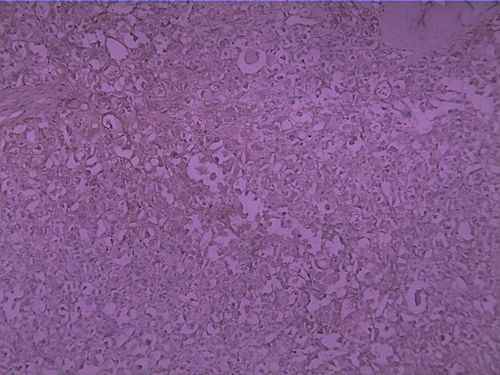

女30Y,大腿肿物5Y,直径3cm

• 女30Y,大腿肿物5Y,直径3cm图1

图1

生长位子比较深,浸润纤维间质之中,诊断圆形细胞脂肪肉瘤 ,查一下免疫组化,S-100,VimE。及PCK排除一下上皮来源的印戒细胞癌。

首选腺泡状软组织肉瘤

腺泡状软组织肉瘤

考虑血管源性恶性肿瘤,图中看到肿瘤样血管结构,腔内见红细胞